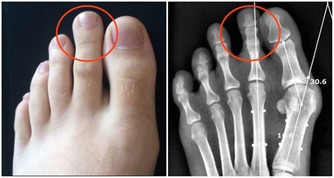

美國一名42歲的男子去非洲奈及利亞旅遊,當時他發現自己腳上的血管變得很清楚。

原本他以為只是類似靜脈曲張所以不在意,但一個月後,他發現這個血管竟然會在他腳步上下移動...

從非洲回到美國後,這樣的狀況並沒以改善,

當時醫生草草看了也說只是普通的靜脈曲張,不用太擔心,所以就讓他回家了。

這名男子也以為自己有靜脈曲張的體質,過了一個月,

他發現這個痕跡越來越淡,但是位置卻跟以前差很多。

保險起見,他決定找了另一位醫生協助,才發現他腳上的紅色痕跡根本不是血管,是巨大的蠕蟲!

蠕蟲時常會藉由貓狗的排泄物傳染,是一種寄生蟲疾病。

醫生也評斷男子可能是赤腳踩在地板上,才感染到這樣的寄生蟲。

在服用抗寄生蟲的藥物後,這名男子已經完全康復。

要防止自己被感染的方法也很簡單,就是記得穿鞋防護、也要避免踩到以排泄物殘留的地方。